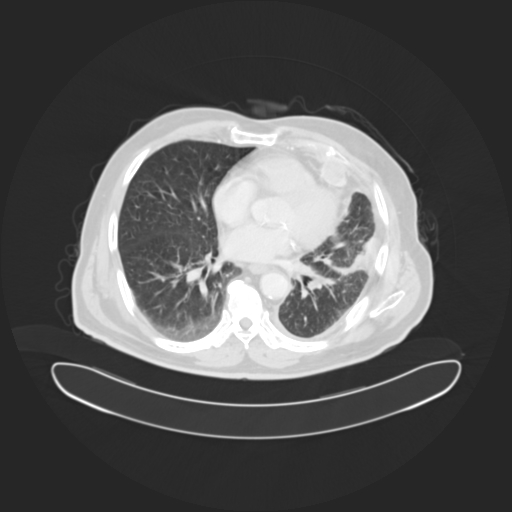

• Analyzes CT scan images using a convolutional neural network

Deep Learning A CNN-based image classifier using a modified ResNet18 trained on lung CT scans.

• ResNet18 model (224×224 RGB input)

Model generalization CT datasets vary significantly in resolution, contrast, and labeling quality. I had to refine preprocessing pipelines to ensure consistent inference.